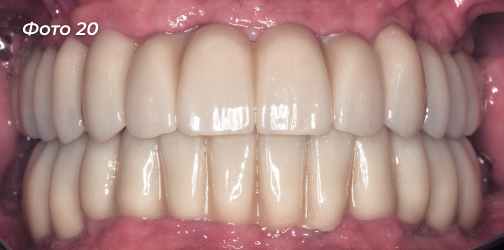

Установлены постоянные конструкции на верхней и нижней челюстях (Фото 18, 19, 20, 21).